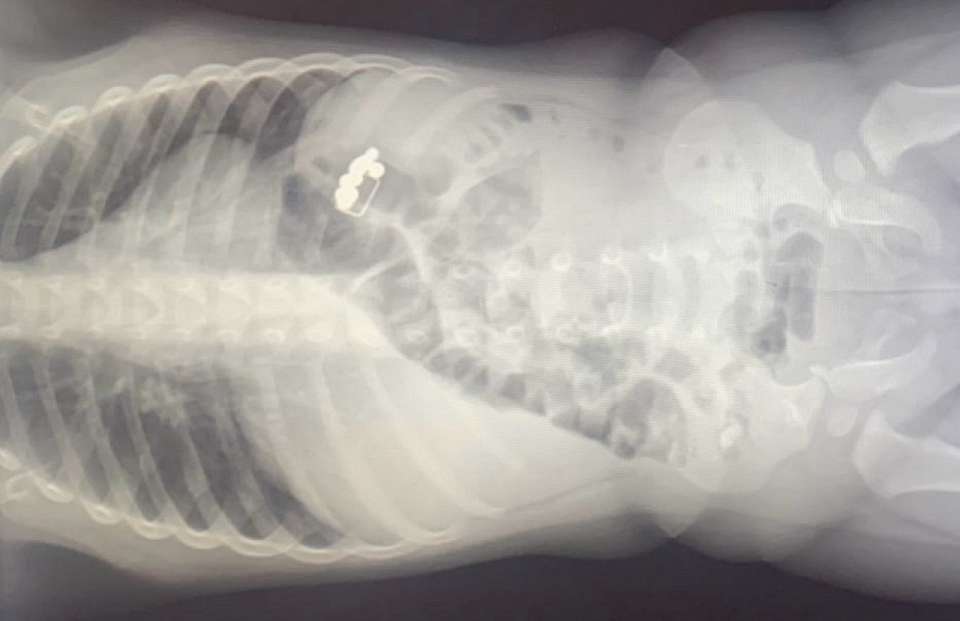

Первоначально предполагалось, что у малыша острая респираторная вирусная инфекция (ОРВИ). Однако, 1 апреля ребёнку провели рентгенографию грудной клетки, на которой в желудочно-кишечном тракте были обнаружены инородные предметы: восемь магнитов и даже канцелярская скрепка.

Малыша направили в Областную детскую клиническую больницу №2 (ОДКБ №2), где детские хирурги подтвердили наличие инородных тел и приняли решение о госпитализации для наблюдения и лечения. Под общей анестезией эндоскопист Александр Климов в срочном порядке извлёк магниты и скрепку. Во время операции были также обнаружены два небольших пролежня на стенке желудка.

После операции был сделан повторный рентгеновский снимок, который выявил наличие ещё двух магнитов. Они вышли самостоятельно после проведения очистительной клизмы.